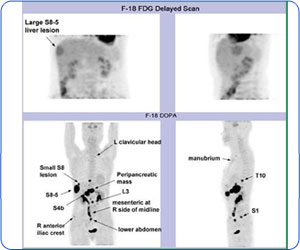

F-18 DOPA scan demonstrates multiple neuroendocrine tumors